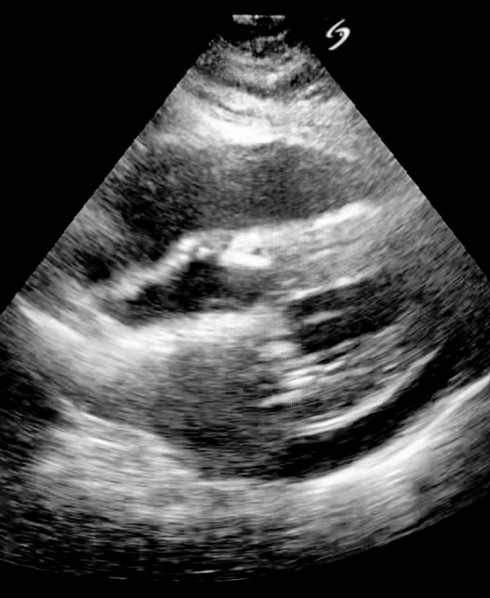

Cardiac tamponade post valve replacement

A 55-year-old man self-presents to your regional ED with new onset shortness of breath on exertion and presyncope post bovine …

2023 Term 3 Wk 7 Archived